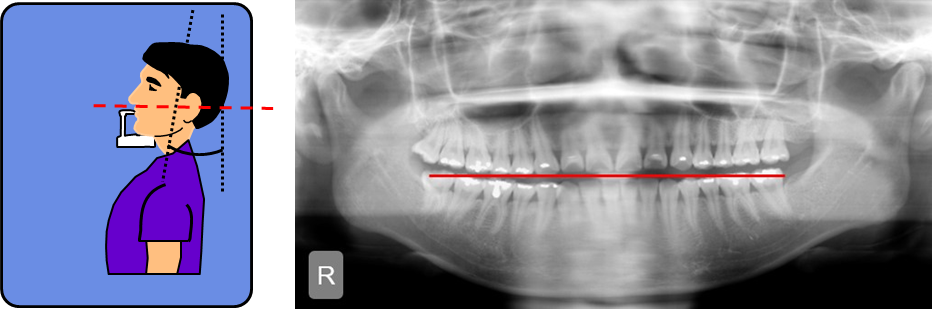

什么是全景片头颅侧位cbct

图片尺寸800x563